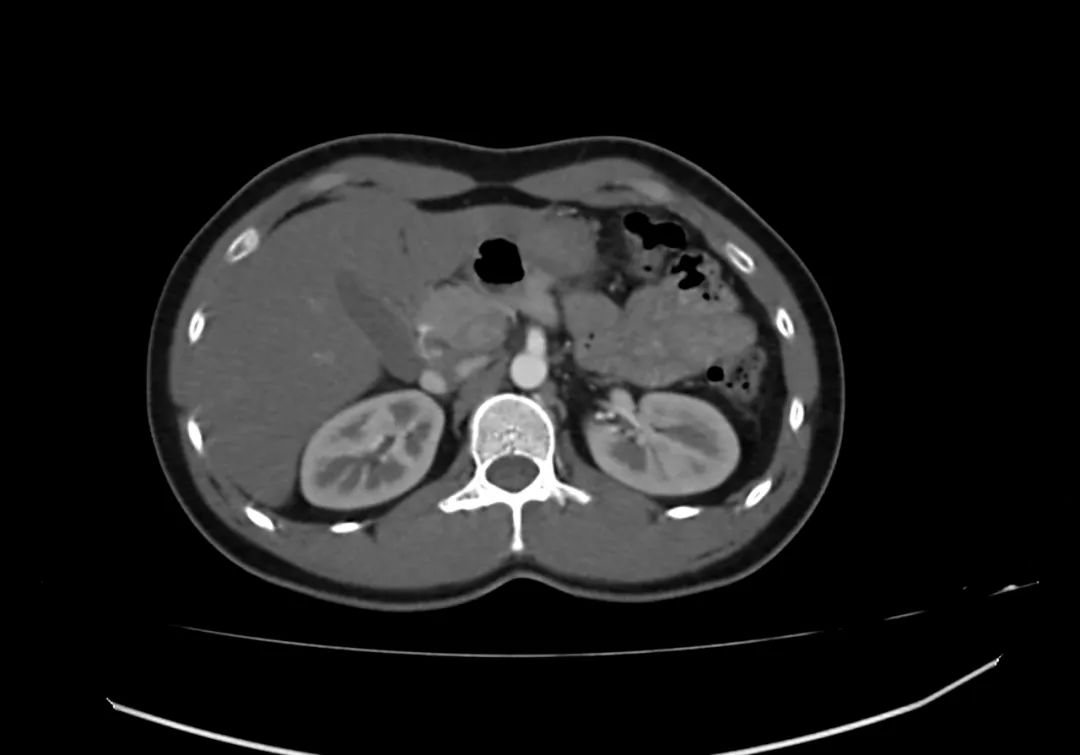

动脉期上腹部轴向增强图像显示胰腺完全包围十二指肠第二部,与完全性环状胰腺一致。

【病例】完全性环状胰腺1例CT影像-1